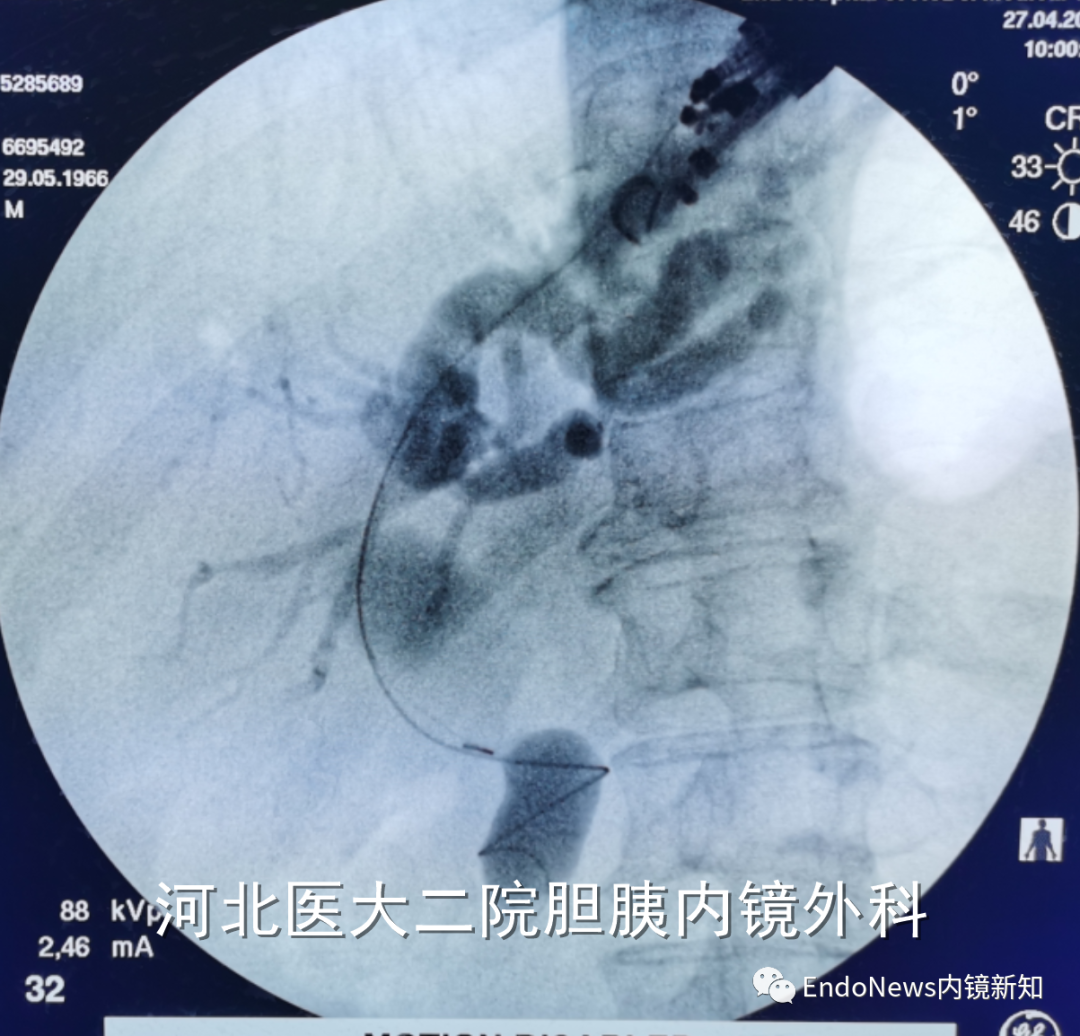

如下图所示,肝门胆管狭窄(Bismuth IV型),导丝进入肝右叶胆管后就可以置入支架引流肝右叶胆管:

取石网篮 为什么贵EUS-BD操作中的细节:导丝如何超选?_https://www.jmylbn.com_新闻资讯_第14张

取石网篮 为什么贵EUS-BD操作中的细节:导丝如何超选?_https://www.jmylbn.com_新闻资讯_第15张